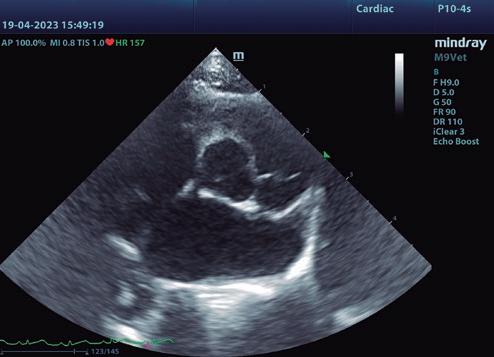

• Modo B: en la proyección paraesternal derecha eje largo, se observó un jet de regurgitación mitral con dirección posterior y SAM (figura 3). En el eje corto derecho a la altura de la base cardiaca se observó un ratio atrio izquierdo/aorta (AI/Ao) de 1,92 (>1,6 se considera dilatación AI) (figura 4). Además, se observó hipertrofia de la pared del septo interventricular (SIV) de 7,6 mm y la pared libre del ventrículo izquierdo (PLVI) la 8,4 mm (hipertrofia >6 mm) (figura 5).

Con el estudio ecocardiográfico, se descartaron las patologías cardiacas congénitas y neoplásicas, degeneración de la VM, endocarditis, y otro tipo de cardiomiopatías.

Con el estudio ecocardiográfico, se descartaron las patologías cardiacas congénitas y neoplásicas, degeneración de la VM, endocarditis, y otro tipo de cardiomiopatías. El diagnóstico definitivo fue fenotipo hipertrófico con SAM y ODTSVI. Como consecuencia de todo ello, se advirtió de la presencia de ICC aguda y descompensada, lo cual nos sitúa en estadio C.